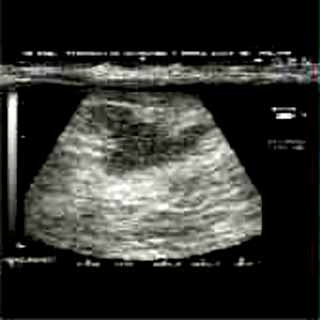

Για την καλλίτερη απόδοση της εξέτασης απαιτείται κεφαλή linear τουλάχιστον 7,5 ΜΗΖ. Ωστόσο και με κεφαλές 3,5 και 5 ΜΗΖ μπορεί κανείς να έχει καλά αποτελέσματα.

Οι απεικονίσεις των περιστατικών που επιδεικνύονται παρακάτω, έγιναν με κυρτές κεφαλές 3,5 και 5 ΜΗΖ, προκειμένου να φανεί, ότι και με τον εξοπλισμό αυτό, που σιγά-σιγά διαθέτουν όλο και περισσότερα ιατρεία, είμαστε σε θέση να έχουμε ικανοποιητικά αποτελέσματα.

Oι τελευταίες 4 απεικονίσεις έγιναν με ειδικό για μαστό ηχοβολέα linear, εναλλασσομένης συχνότητος 7,5-10ΜΗΖ.